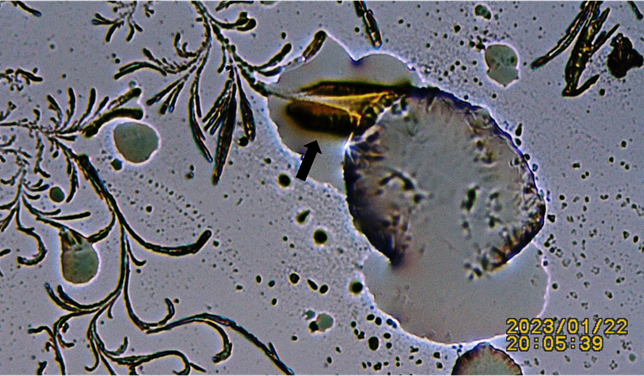

Figure 6

Figure 6 Additional Figure Showing Advancing Crystals Perforating Lipid Droplet. Black Arrow: Notice the Appearance of an Electrical Discharge between Lipid Droplet and Advancing Crystal. |